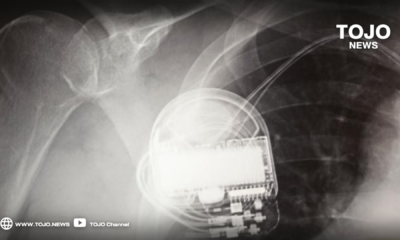

กรมการแพทย์ เผยแล้ว! ปัญหา...